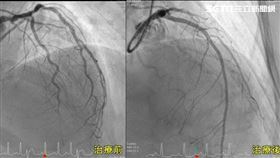

壞膽固醇飆塞爆血管 45歲女心衰竭

台中45歲張女士因心臟衰竭緊急就醫,初步檢查發現三條...

2020/04/21 10:02